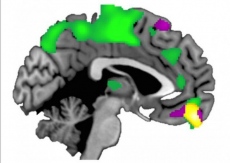

![[Img #26710]](upload/img/periodico/img_26710.jpg)